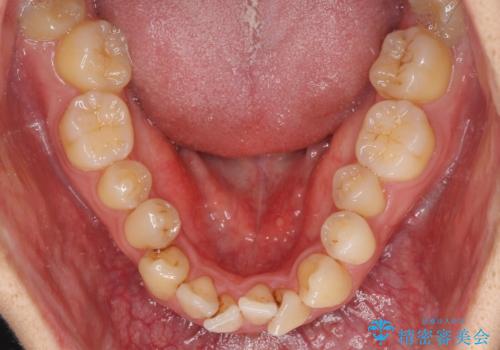

下顎の歯列全体が右側にずれているため、右下のみ第二小臼歯を抜歯し、上顎は補助装置を使用して、極力上下の正中を合う位置にて咬み合わせを改善するようにしました。

元の歯列が想像できないほど、きれいな歯列に整えることができました。

第二小臼歯抜歯の矯正治療は、治療期間が長引くことが多いですが、動きが非常に良く、予定の治療期間で終えることができました。